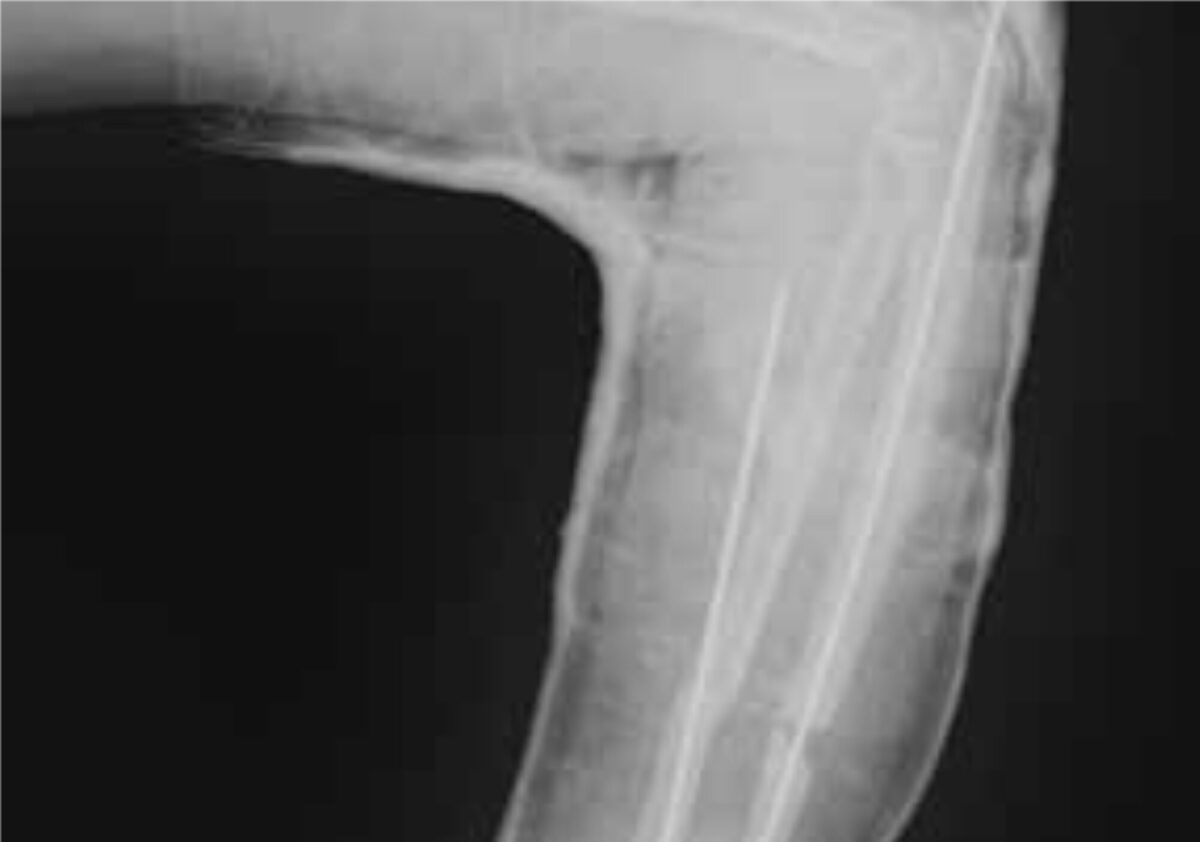

The above-mentioned possibilities were discussed with the patient and he preferred to be operated in The Lion Heart Medical centre at short notice. With the help of detailed instructions from the specialists the procedure was carried out. In theatre, the old callus was scraped away from the fracture ends and both the radius and ulna were fixated with metal pins (k-wires). Unfortunately the X-ray (figure 2) showed that the pin through the radius was misplaced and therefore had to be removed immediately after the procedure. POP was applied to the upper and lower left arm for six more weeks, after which the second pin was removed. POP was applied again for three more weeks.

Nine weeks after surgery the POP was removed. Clinically the ulna was reunited, but the radius was not, probably due to misplacement and removal of the metal pin.

Unfortunately at that moment the X-ray device was out of order, so imaging of the final result was not available. However, most importantly the left arm was functional again. The wrist joint functioned normally and flexion and extension of the elbow joint was also possible. Pronation and supination of the lower left arm were restricted due to instability of the radius. The main outcome was that the patient was able to grab and hold objects again with his left arm due to the stability of the ulna. Therefore the patient was very pleased with the final outcome.